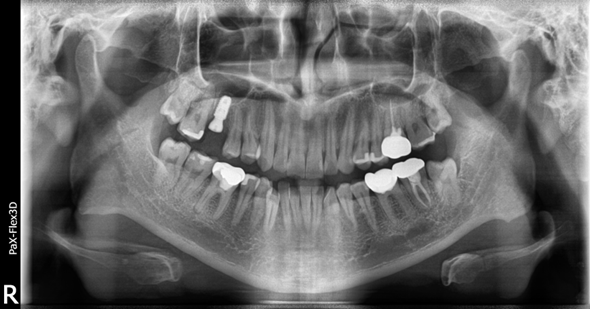

30대 남성

(전) 2022-05-10 (후) 2022-08-25

왼쪽 위 어금니를 발치하고 임플란트 진행하신 환자분인데요.

잇몸뼈의 높이가 충분하지 않아 상악동거상술 및 뼈이식을 진행하고 3개월 후 임플란트를 식립했습니다.